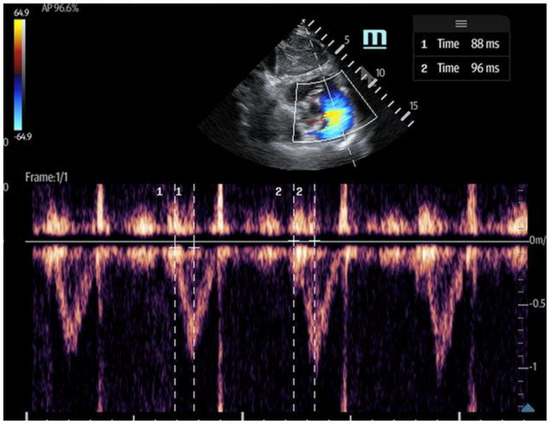

- The 60/60 sign: This is an echocardiography sign that refers to the presence of both pulmonary acceleration time (PAT) ≤60 milliseconds (Figure 9) and tricuspid pressure gradient ≤60 mmHg as a marker for acute RV strain in acute PE, although it has poor sensitivity [52]. It is thought to be more advantageous than McConnell’s sign due to its objectivity and reproducibility [50]. The 60/60 sign has a sensitivity of 36% and a specificity of 94% when seen in combination with McConnell’s sign, emphasizing the utility of various ultrasound findings when assessed in conjunction with each other [50].